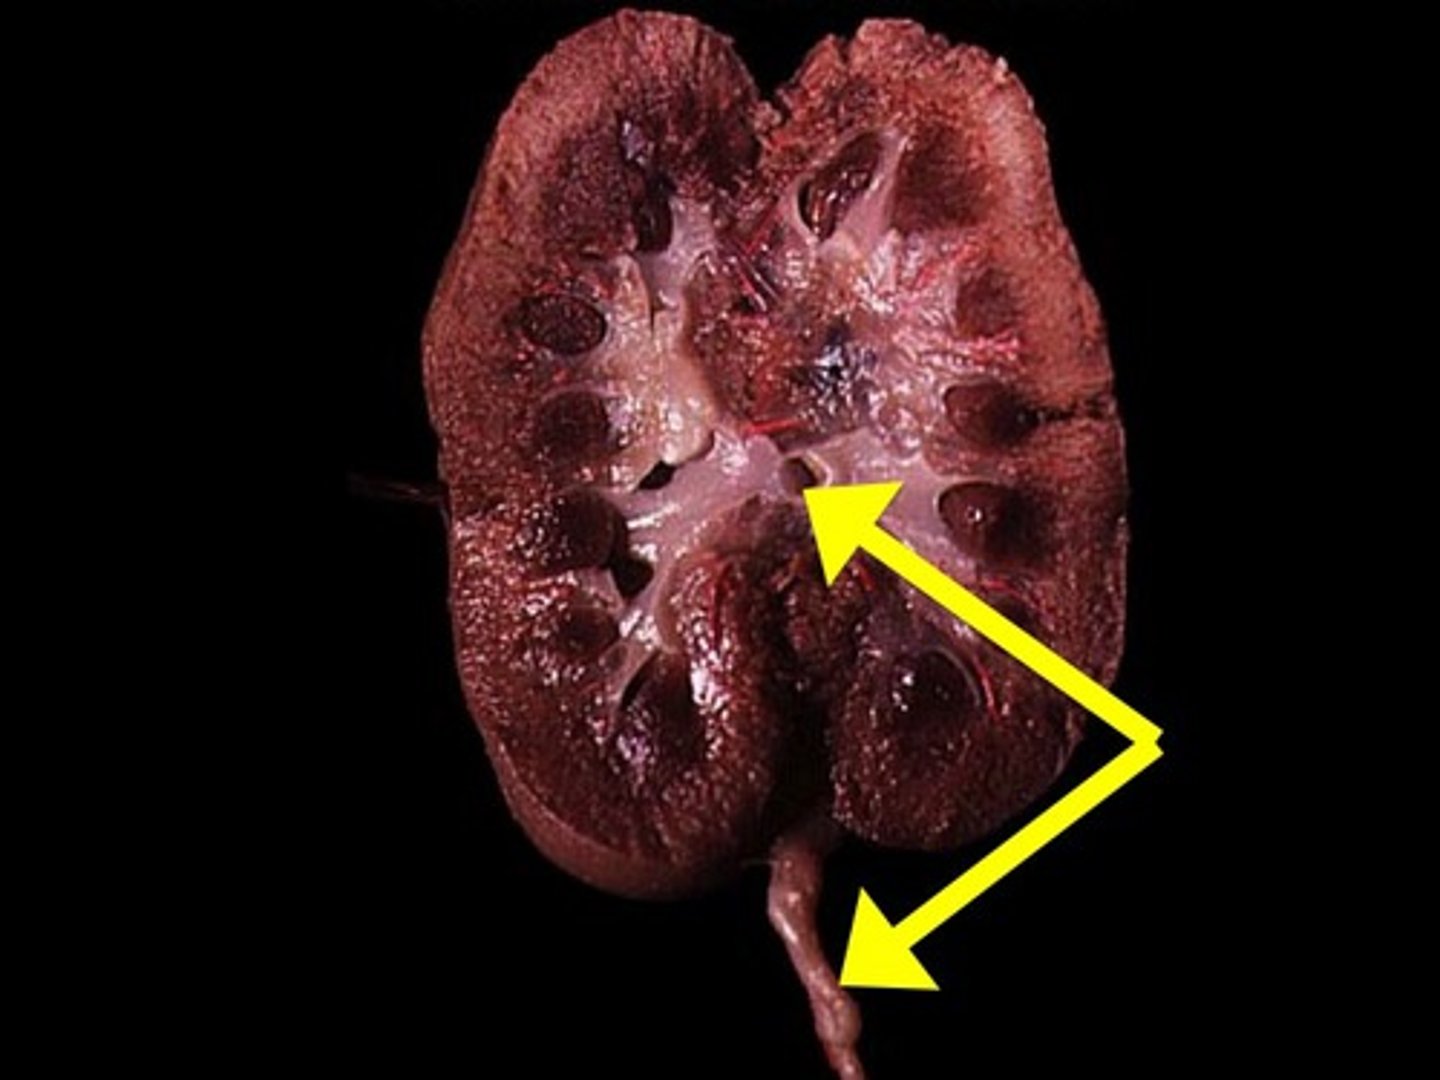

Renal Cortex

Renal Medulla

Renal Pyramid

Renal Column

Renal Pelvis

Ureter